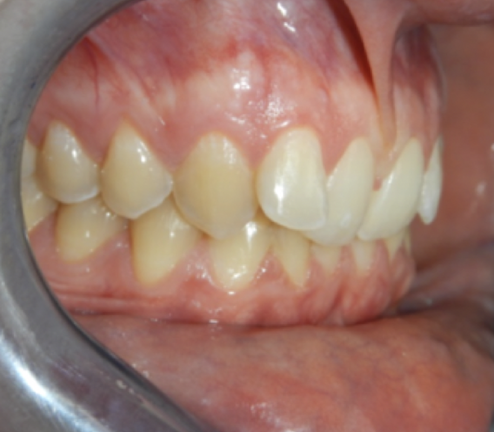

CHEVAUCHEMENT DES INCISIVES

ADÈLE 22 ans

Réaligner les incisives et réduire la supraclusion

Classe I squelettique – Profil orthofrontal – Classe I dentaire – DDM – Supraclusion incisive – 12+22 ectopiques

– Palatoversion des 11+21

PHOTOS AVANT /APRÈS TRAITEMENT